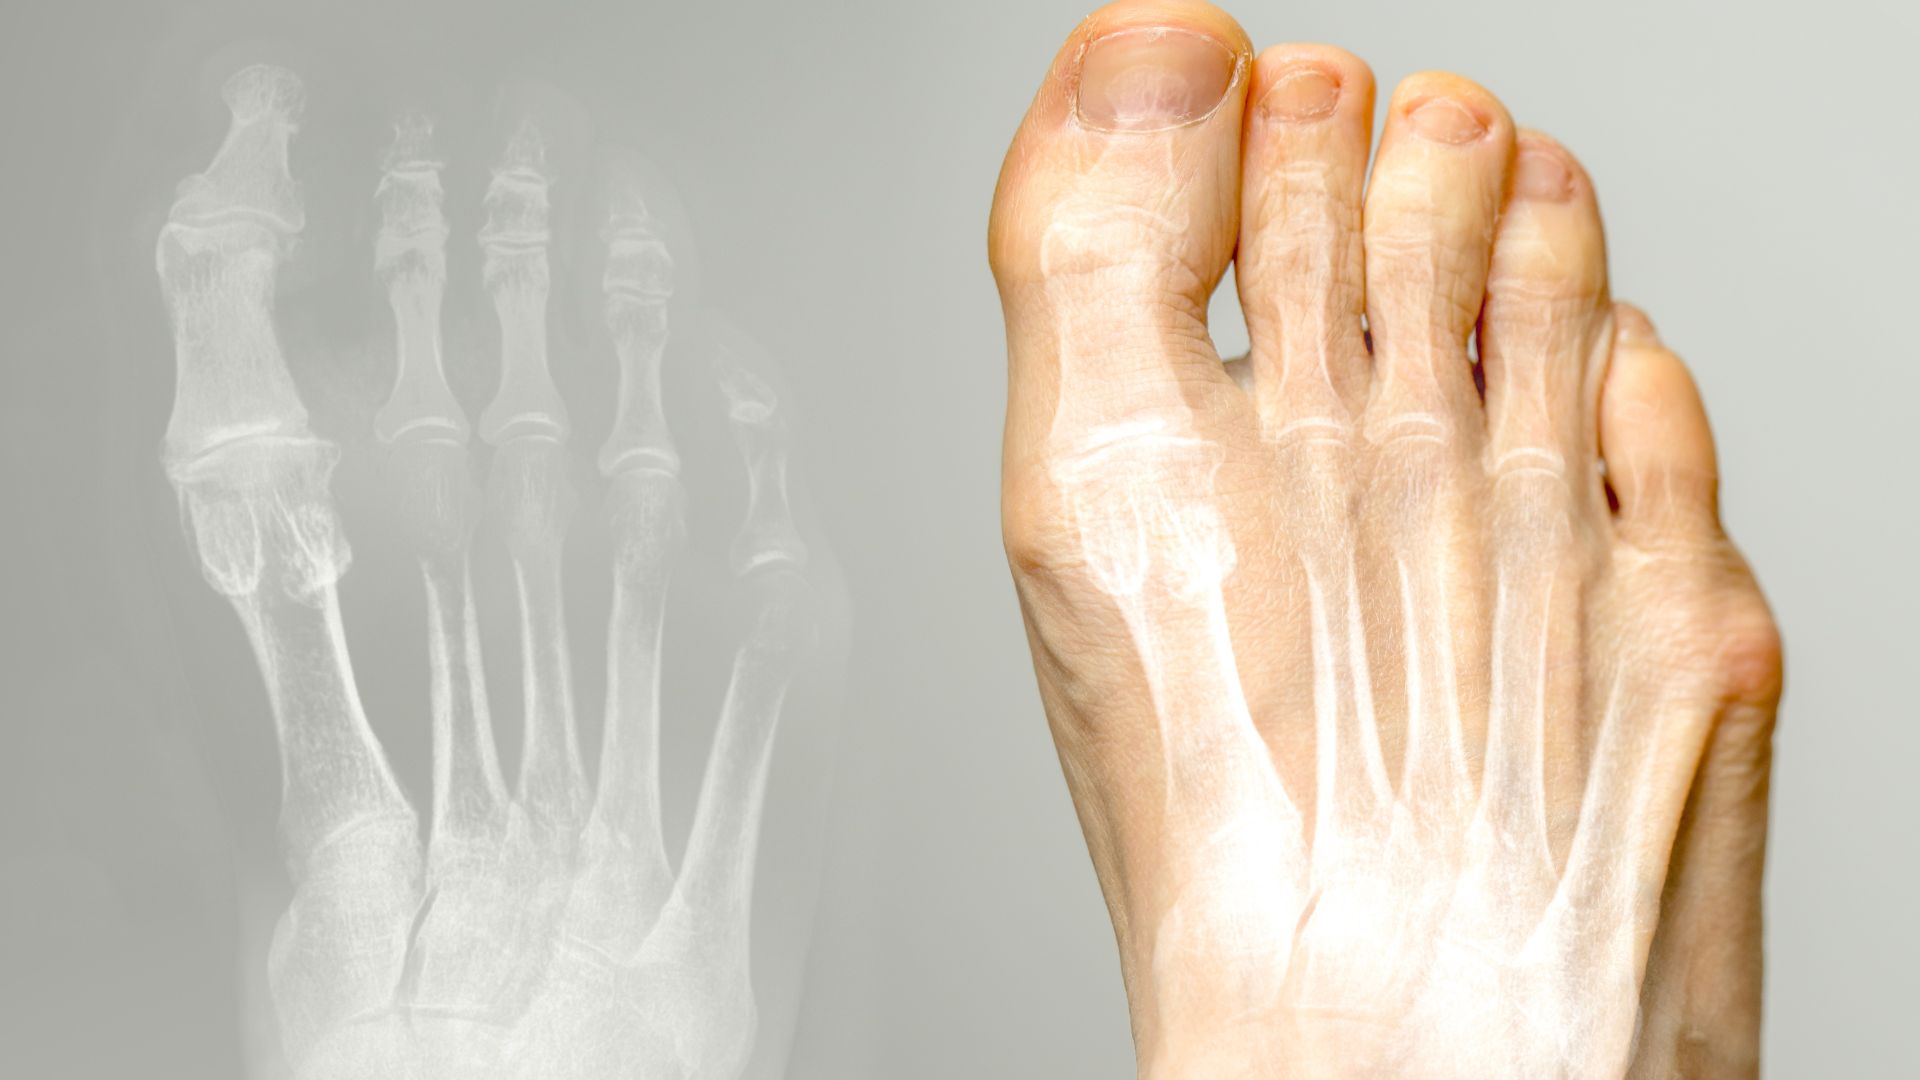

Nghi ngờ biến dạng hoặc bất thường cấu trúc

Khi bàn chân xuất hiện dấu hiệu lệch trục, cong vẹo ngón hoặc thay đổi hình dạng so với bình thường, bác sĩ có thể chỉ định chụp X-quang để đánh giá chính xác cấu trúc xương và mức độ ảnh hưởng. Hình ảnh thu được giúp xác định bản chất bất thường, hỗ trợ xây dựng kế hoạch điều trị chỉnh hình phù hợp và theo dõi diễn tiến bệnh lý theo thời gian.